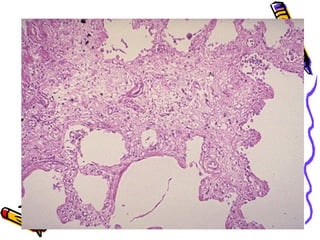

Idiopathic pulmonary fibrosis

• This is characterised by diffuse

interstitial inflammation and fibrosis

resulting in severe hypoxemia and

cyanosis in the late stage

Morphology(contd..)

• END-STAGE:-

• Spaces lined by cuboidal /columnar

epithelium separated by

inflammatory fibrous tissue(Honey-

comb lung)

• (end stage lung same in all conditions)